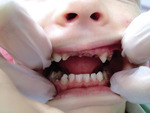

Próchnica wczesna (caries praecox) jest to typ próchnicy charakterystyczny dla dzieci najmłodszych. Amerykańska Akademia Stomatologii Dziecięcej (AAPD) i Towarzystwo Stomatologów Amerykańskich (ADA) określiło mianem próchnicy wczesnej (ECC – early childhood caries) stan, w którym stwierdza się obecność jednego lub więcej zębów mlecznych dotkniętych próchnicą, usuniętych z jej powodu lub wypełnionych u dziecka do 71. m.ż. (ryc.1).[2]